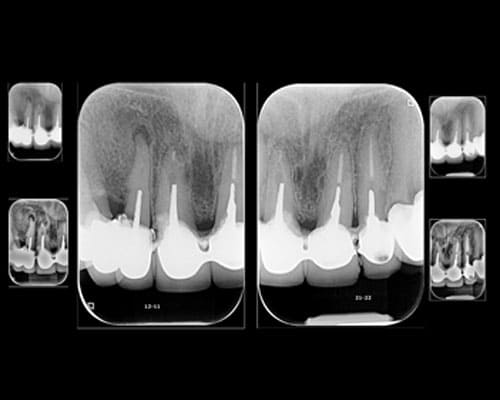

RADIOGRAFIA 2D INTRAORAL

PERIAPICAL DIGITAL AMPLIADA

PERIAPICAL MILIMETRADA

JUEGO PERIAPICAL